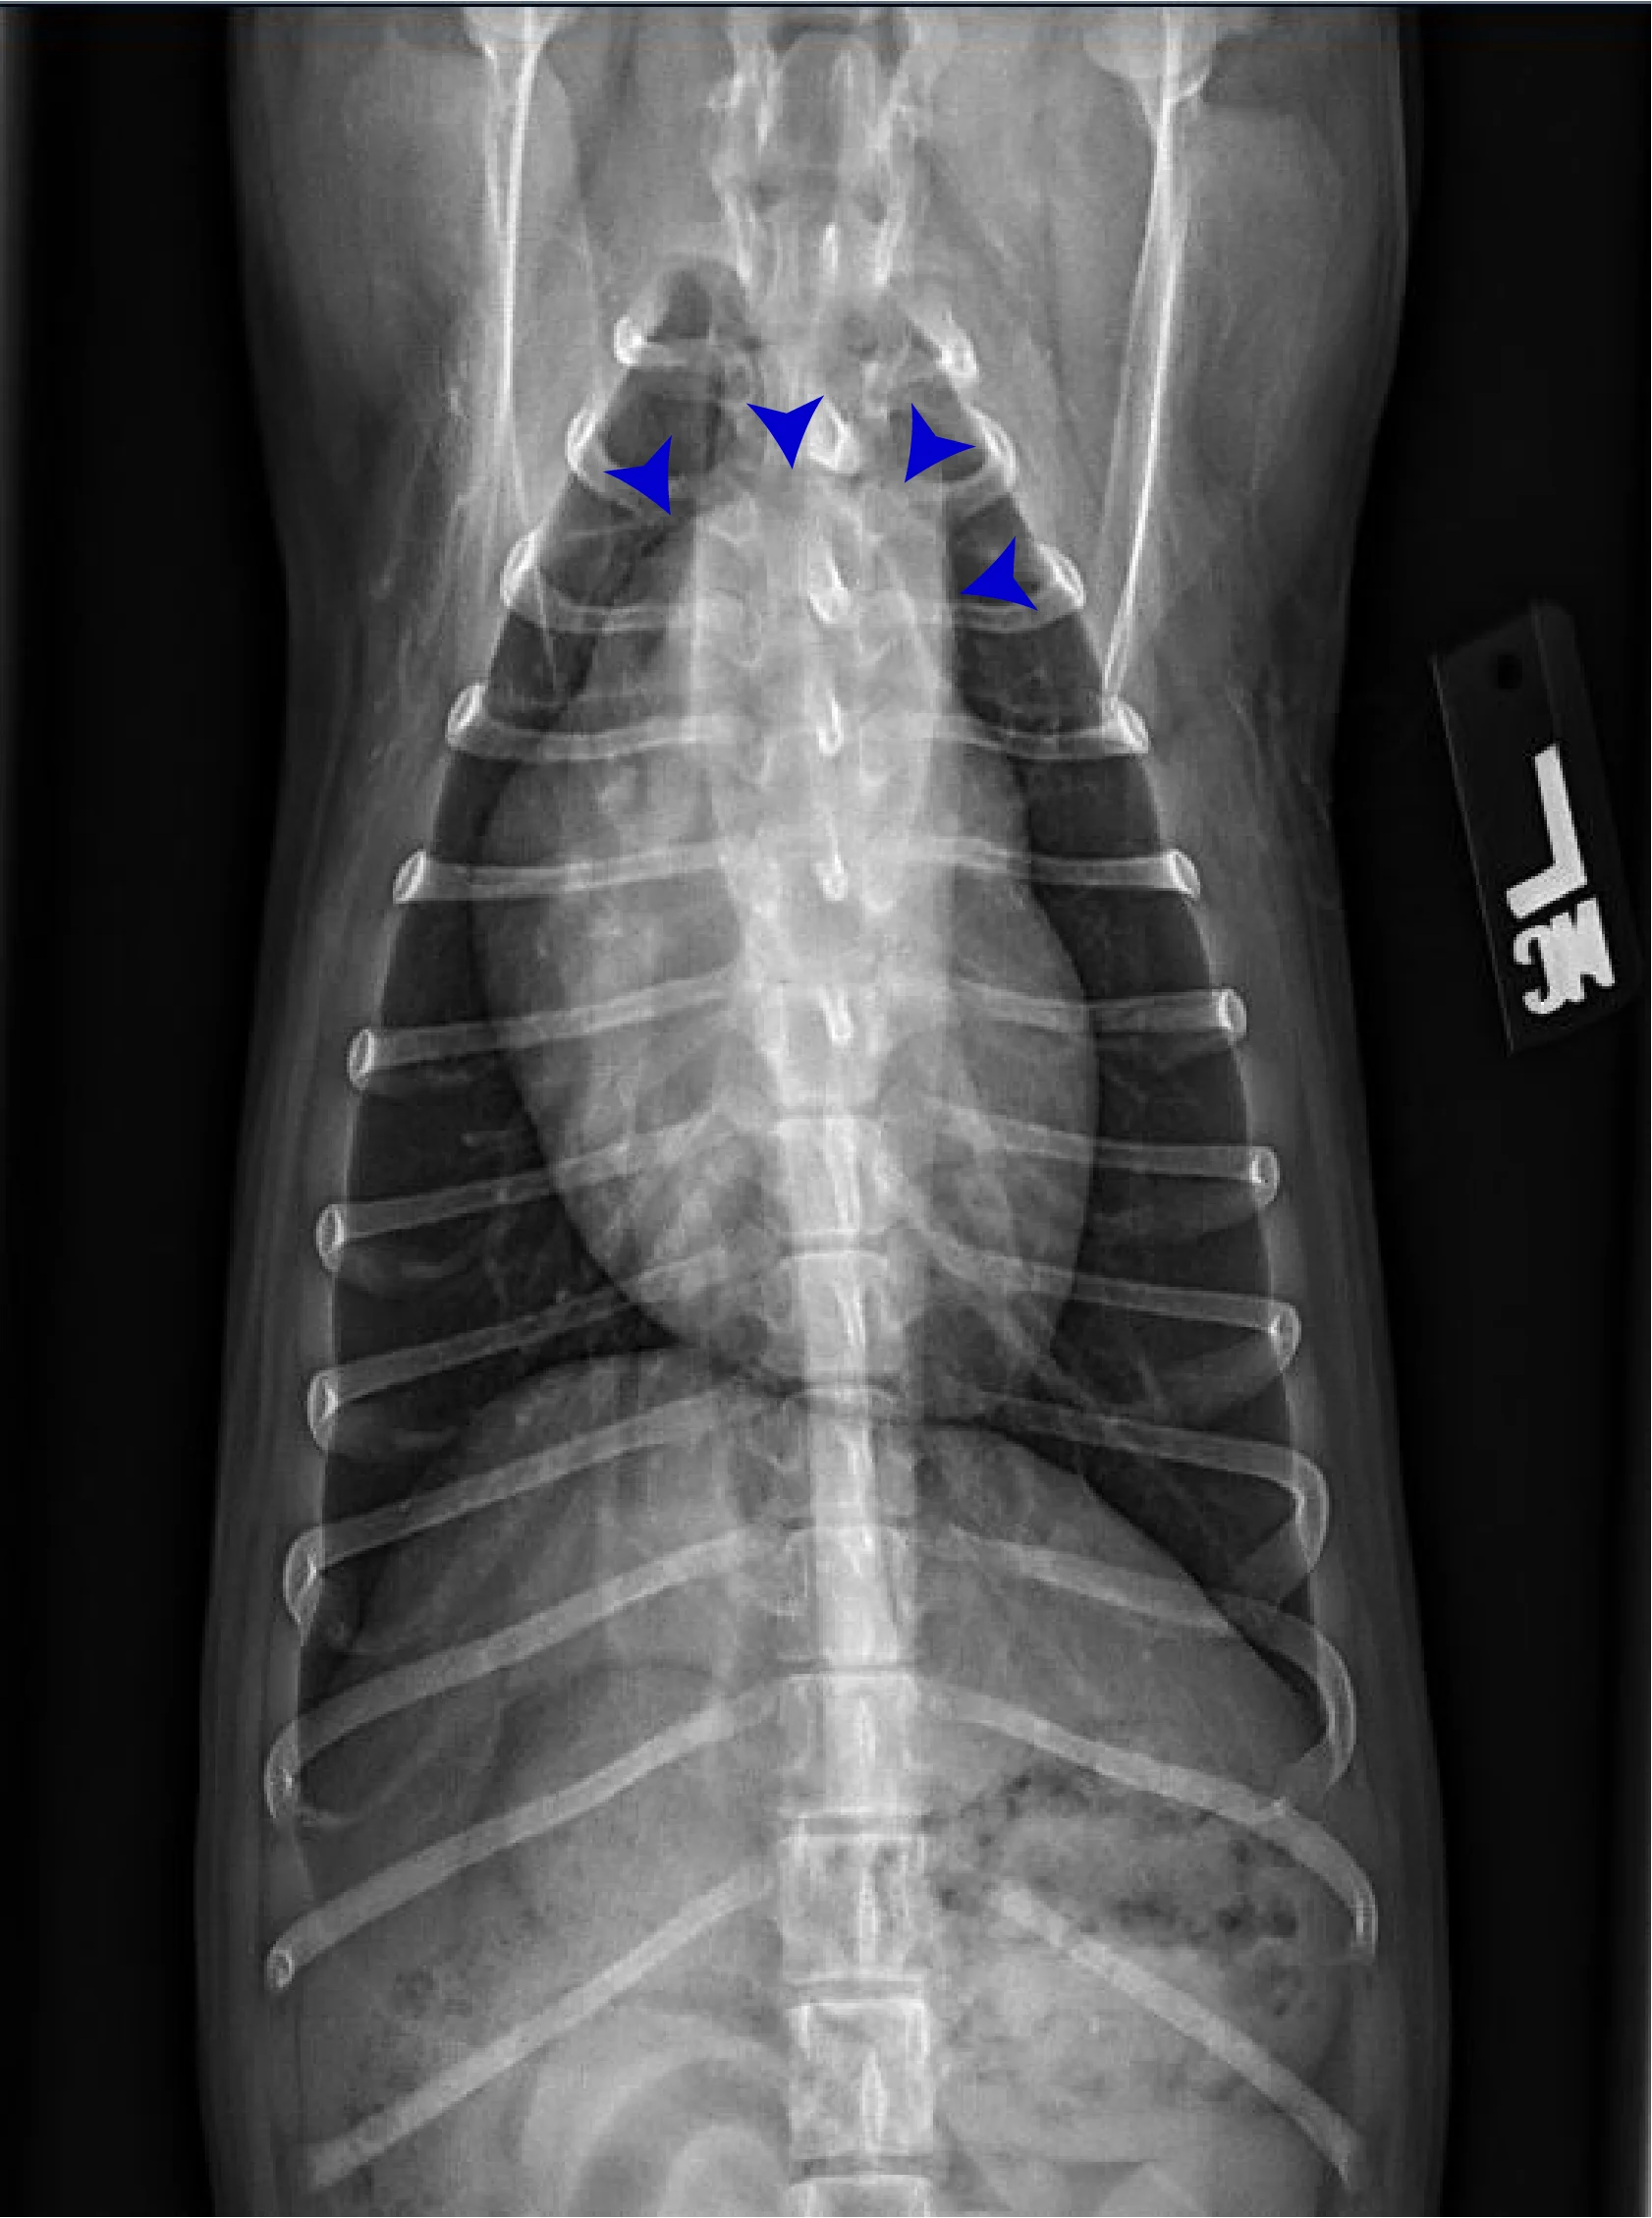

FIGURE 2 Normal DV (left) and VD (right) projections of the thorax in a large, crossbreed dog. The cardiac silhouette appears more rounded, and the caudal pulmonary vasculature is more apparent (arrowheads) in the DV view compared with the VD view. In some DV projections, the cardiac silhouette can appear significantly displaced to the left (not apparent in this case). Images courtesy of Federico Villaplana Grosso, DACVR, DECVR